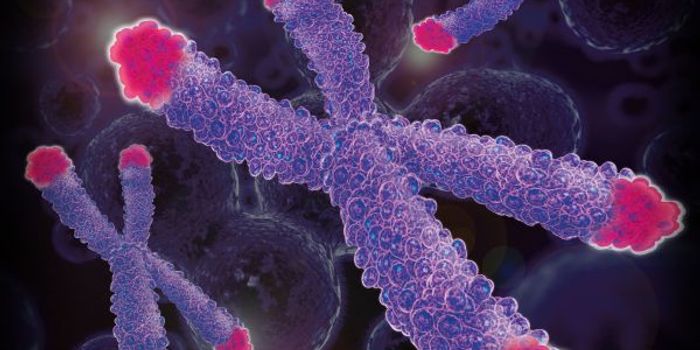

JUL 15, 2015Genetics & GenomicsThe role of telomeres in the aging process has become a hot topic in biology, and recent study have linked telomeres - t ...

FEB 21, 2023Cell & Molecular BiologyThe Griffith Lab at UNC discovered telomeric protein & potential biomarker VR (green), shown in the nuclei (blue) of hum ...